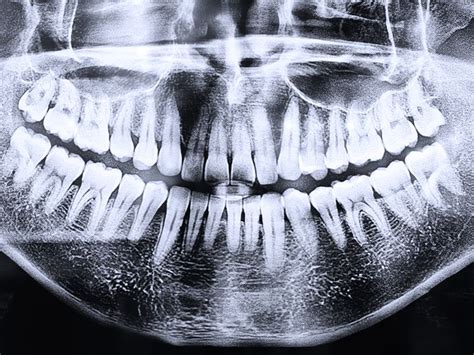

En ortodoncia, la radiografía panorámica, al igual que la telerradiografía lateral de cráneo, es fundamental para diagnosticar problemas. Sin ellas, el ortodoncista no puede diagnosticar adecuadamente ni preparar un plan de tratamiento correcto. Valorar las raíces de los dientes también es muy importante a la hora de elaborar un correcto plan de tratamiento en ortodoncia.

En los tratamientos de ortodoncia, las pruebas radiológicas se utilizan con frecuencia para diagnosticar patologías relacionadas con los dientes. Por ejemplo, la radiografía panorámica y la telerradiografía del cráneo son dos de las pruebas más importantes. A través de la radiografía el ortodoncista puede encontrar las patologías pertinentes, pero también observar la posición y la forma de dientes y mandíbula.

Los ortodoncistas utilizan estas imágenes diagnósticas para planificar de manera efectiva el tratamiento adecuado. Por ejemplo, para obtener una visión integral de la boca, es posible hacer una radiografía panorámica con brackets, lo cual es esencial para evaluar tanto los dientes como la mandíbula en su totalidad.

- Radiografía panorámica: Ofrece una visión general de los dientes y los huesos maxilares.